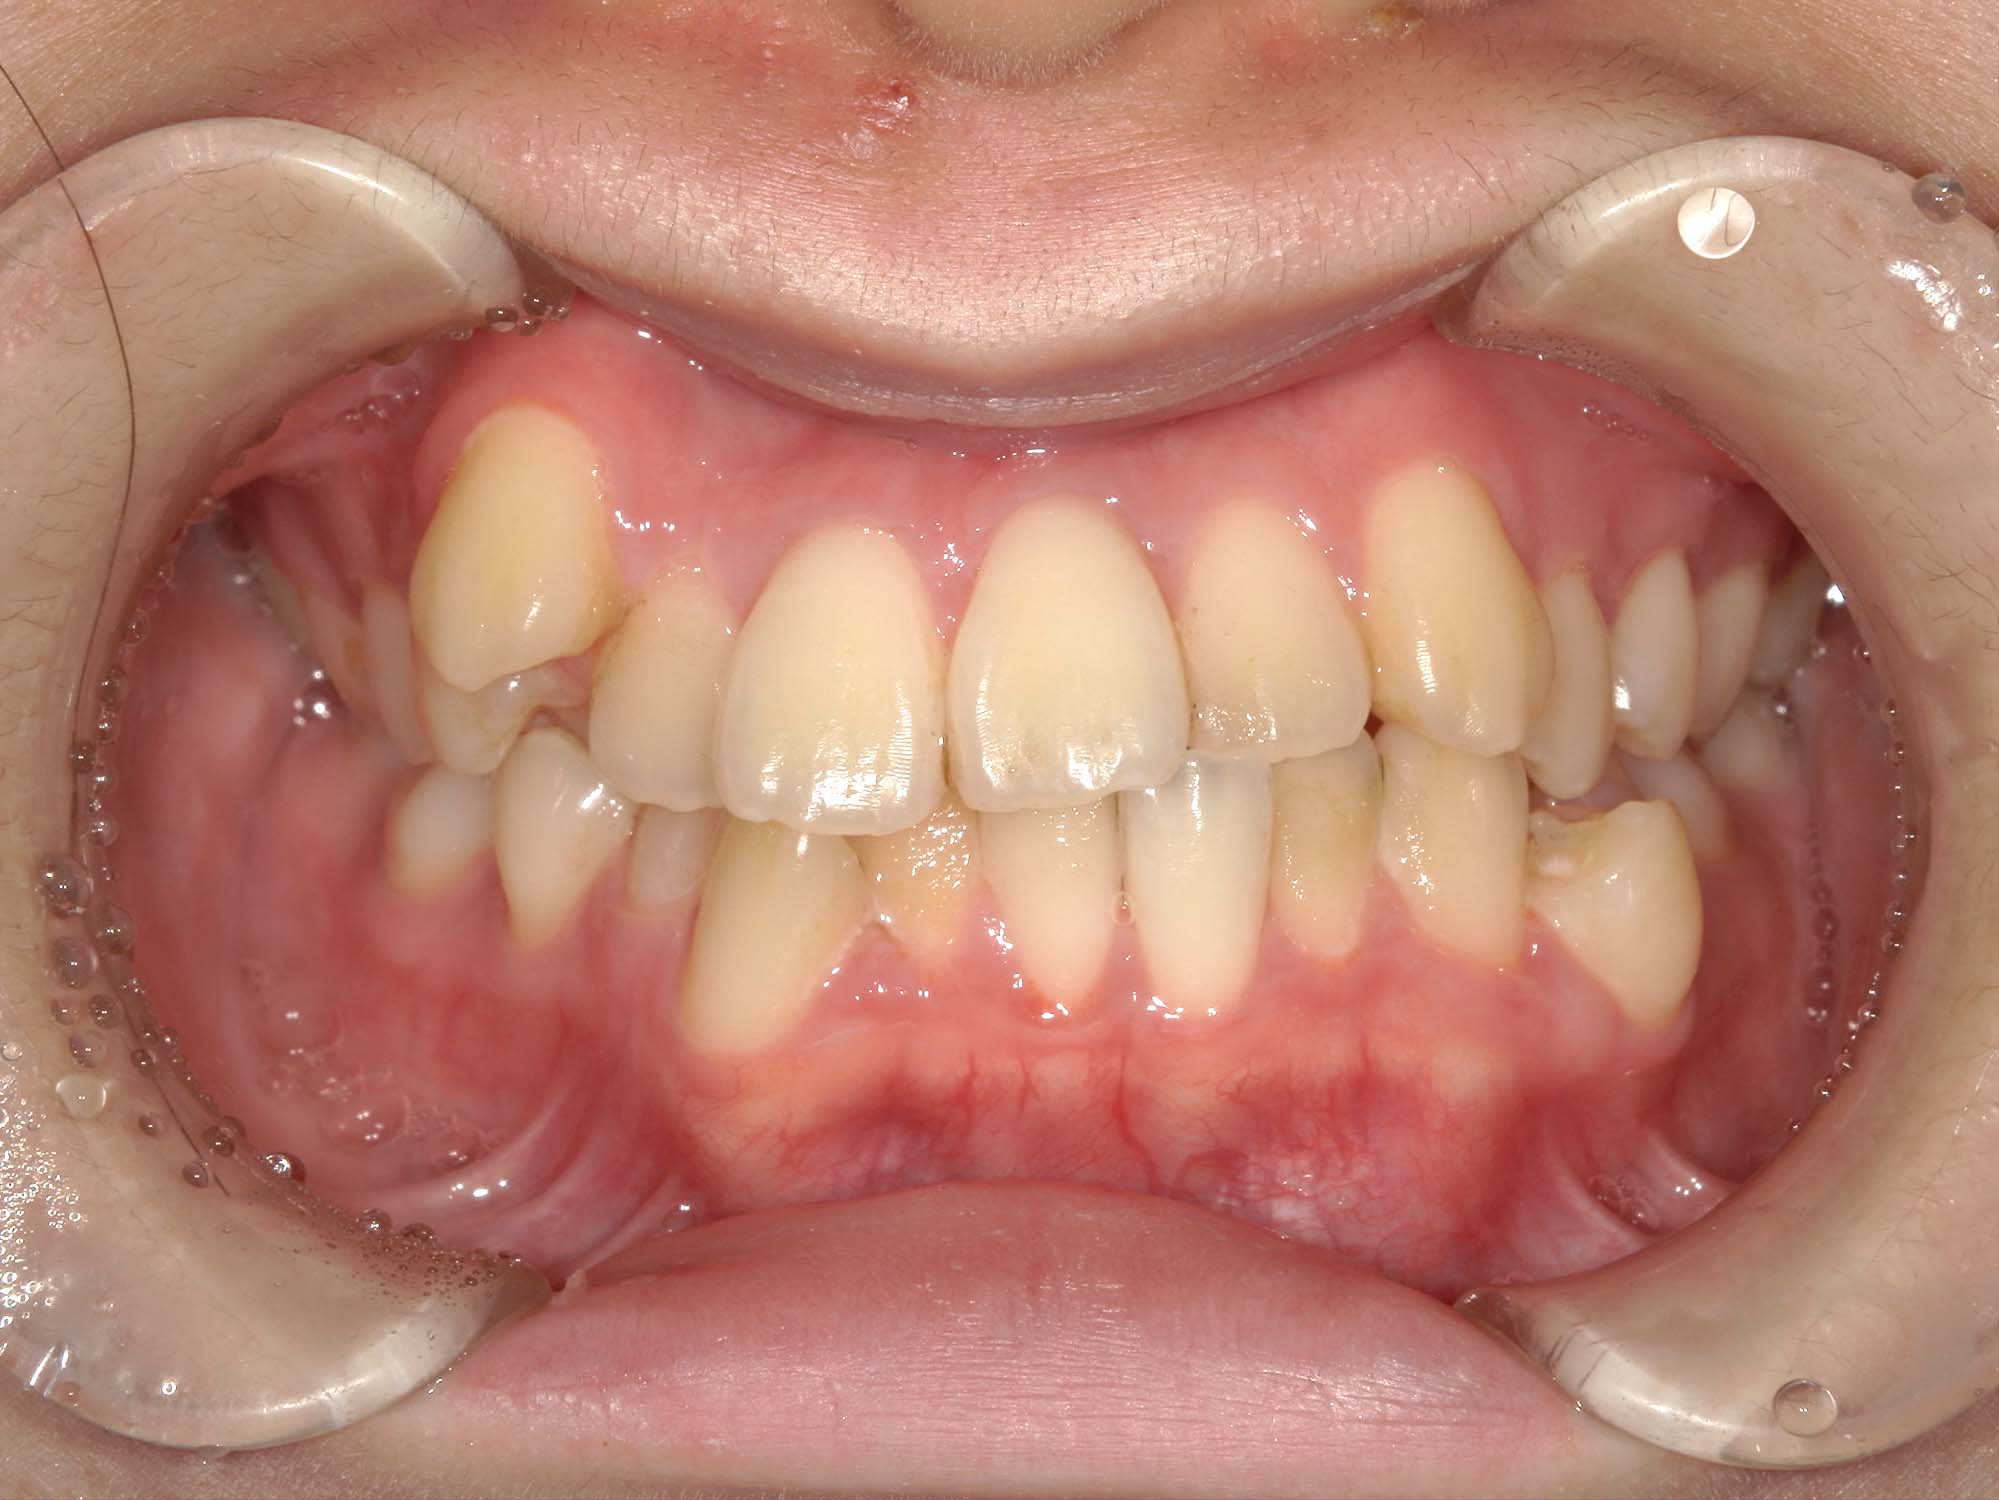

| 年齢・性別 | 15歳の女性 |

|---|---|

| 主訴 | 咬み合わせが逆であること(反対咬合)を気にされて来院された15歳7か月の女性。見た目や機能面の改善を希望されていました。 |

| 治療期間・回数 | 4年4ヶ月・28回 |

| 費用 | 900,000円 |